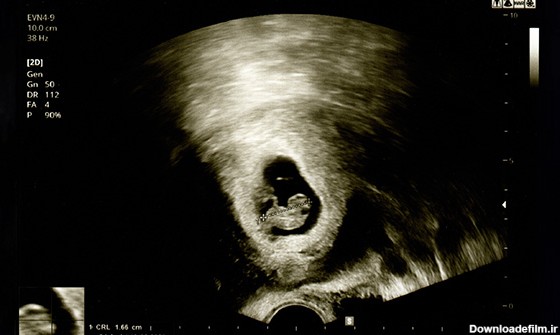

اندازه جنین یک ماهه کوچکتر از یک دانه برنج است! اما در ماه اول بارداری خصوصیتهای ژنتیکی شکل میگیرد. آیا جنین یک ماهه جفت دارد؟ | عکس جنین یک ماهه در شکم مادر

تصاویر سونوگرافی سه ماهه اول جنین – هفته هفتم تا دوازدهم این محیط برای رشد و نمو همچنین حرکت جنین است مایع آمنیوتیک جنین را از هر گونه فشار خارجی روی شکم محافظت می...